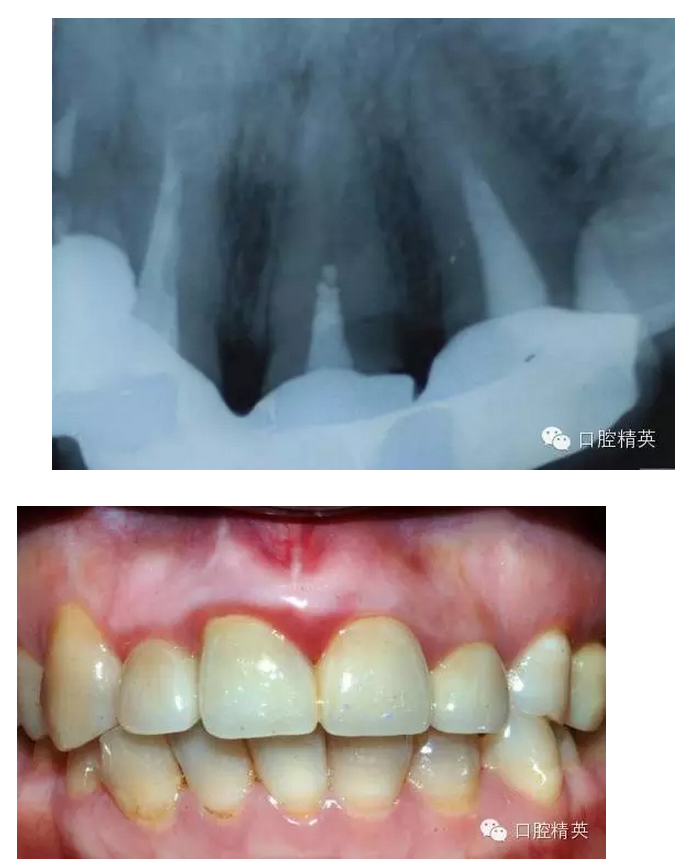

最近接到這樣一位患者,上前牙氧化鋯聯(lián)冠修復(fù)不足一年時(shí)間,現(xiàn)患者主訴左上前牙疼痛來診,檢查發(fā)現(xiàn)上前牙冷熱無反應(yīng),扣診(++),牙齦紅腫,探出血,冠邊緣不密合, X片示基牙全部已做根管治療,但是根管充填全部欠填。

病例1 由于根管充填不完善造成修復(fù)體拆除

修復(fù)后出現(xiàn)根尖周炎癥狀 根管再治療后病變愈合